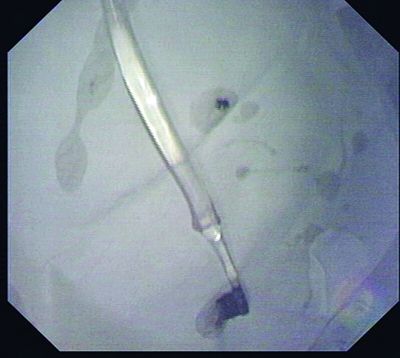

陈洁等医师最终确定的方案是:使用网篮(一种一头带有伸缩金属丝的套取工具),先套住牙刷柄的最末端,努力收紧往上提,到喉咙口时让姜女士头部尽量向后仰,顺着食道方向取出牙刷。

下午2点左右,医生开始“行动”了。然而实际操作远比想象的难得多。由于牙刷柄末端太滑,很难套;牙刷也太长,很难出喉咙口,但好在这个思路和方向没有问题,几个关键行动:套取刷柄、出喉咙口都先后得到解决。一个半小时的鏖战,这支“失足牙刷”终于被逮了出来。